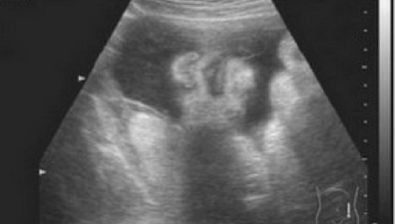

Ultrasound at 34 Weeks

34 Weeks Pregnant: With Twins

According to statistics, most twin or multiple pregnancies don’t last past the 37th week.

Of course, this is just another average. But, it’s an average that you may very well be a part of soon.

Right now, you’re just working on keeping those babies in there as long as you can. And, trying to keep yourself as comfortable and healthy as possible.